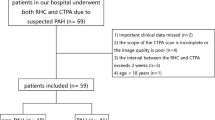

This retrospective study was approved by the institutional review board. Informed consent requirement was waived because of its retrospective nature. Records of all patients undergoing RHC, CTPA and transthoracic echocardiography for the initial diagnostic workup of suspected pulmonary hypertension in our institution between August 2013 and June 2015 were retrospectively reviewed (n = 94). Exclusion criteria were signs of chronic thromboembolic disease on CTPA (n = 13), an interval between CTPA and RHC of more than 30 days (n = 3), non-diagnostic CTPA (n = 3), missing RHC measurements (n = 1) or missing echocardiographic PASP measurements (n = 4) resulting in a final study population of n = 70 (Table 1). Signs of chronic thromboembolic disease on CTPA was chosen as an exclusion criterion because intraluminal thrombi can be expected to decrease the contrast-enhanced vessel lumen thereby resulting in falsely low vessel volume measurements. Patient characteristics (gender, height, weight, age) were extracted from the records; body surface area was calculated according to the formula by Du Bois and Du Bois [22].